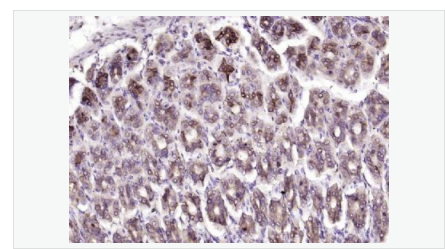

image.png